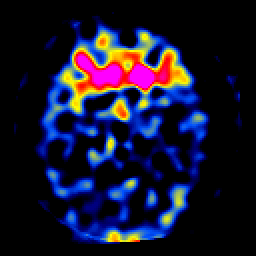

SPECT TL Study #7 -- Slice #20